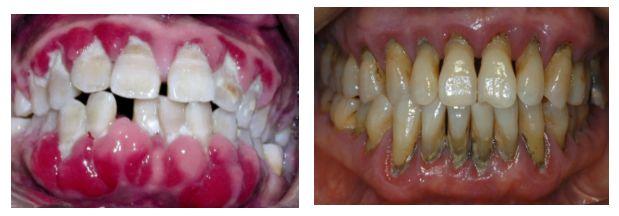

口腔中有没治疗的龋齿、残根、残冠、不良修复体、牙龈炎、牙周炎及口腔粘膜病等都可以引起口臭。

牙周炎患者常伴有大量的牙石、菌斑,牙周袋内细菌发酵产生硫化氢、吲哚和氨类,也会产生臭味;

牙周脓肿和牙周袋溢脓,多为金黄色葡萄球菌合并牙周致病菌感染,也会发出臭味;